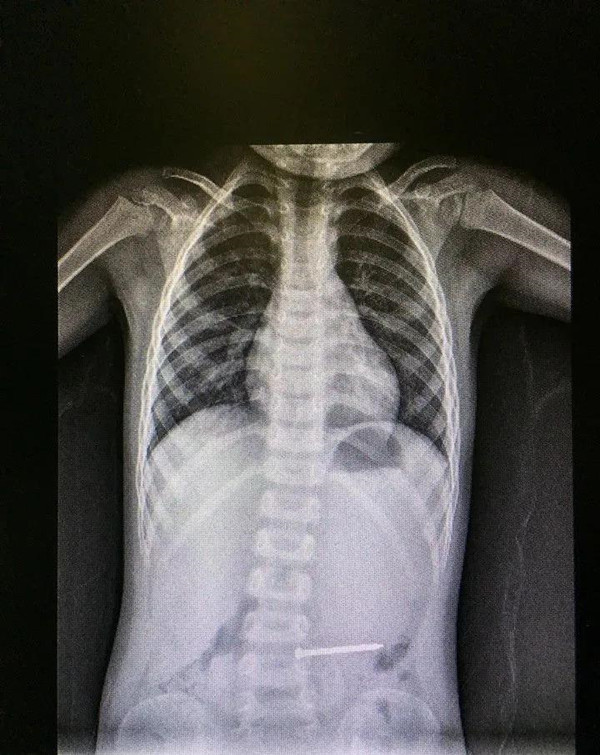

急診科醫生接診,詳細詢問了孩子的病史、進食情況及目前癥狀。放射科開通綠色通道為翔翔作DR檢查,發現鐵釘橫在孩子的左側中腹部。隨后,急診醫生將孩子安排在搶救室,并請消化內科、普外科、麻醉科進行急會診。

經會診評估,鐵釘位于中腹部無法判斷位于胃內還是已經進入腸道,且患兒有腹痛、腸鳴音減弱表現。安全起見,決定先行腹部CT檢查評估鐵釘位置,行急診內鏡下金屬異物取出術,同時作好開腹異物取出術前準備。

經過四個科室的通力合作,下午1點38分,5cm長的鐵釘順利通過內鏡取出。半小時后翔翔蘇醒,安全返回普外科病房進行后續觀察。因為取出及時,除了鐵釘造成局部胃黏膜少許擦傷,翔翔并沒出現消化道出血、穿孔等并發癥。